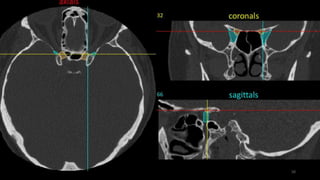

LEVEL-10

COCHLEA

INTERNAL AUDITORY CANAL

MIDDLE EAR WITH MALLEUS AND INCUS

SQUAMO OCCIPUT

Occipitomastoid suture

BODY SPHENOID

GREATER WING SPHENOID

Space connecting superior and inferior orbital

219

PETROUS TEMPORAL